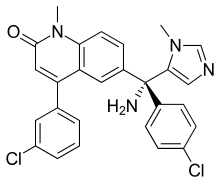

Studies have been published indicating that farnesyltransferase inhibitors such as lonafarnib a synthetic tricyclic derivative of carboxamide with antineoplastic properties can reverse instability of nuclear structure due to the genetic mutation of the LMNA gene. The drug has been used to treat children suffering from Hutchinson–Gilford progeria syndrome.[6] Results of the first-ever clinical drug trial for children with progeria, demonstrated the efficacy of a farnesyltransferase inhibitor (FTI). [7]

| Lonafarnib | SCH66336 | 193275-84-2 | |

| Tipifarnib | sc-364637 | Tipifarnib has been shown to inhibit farnesyltransferase and therefore the kappa B-Ras peptide. Tipifarnib has also been shown to increase apoptosis in certain cancerous cell lines. | 192185-72-1 |